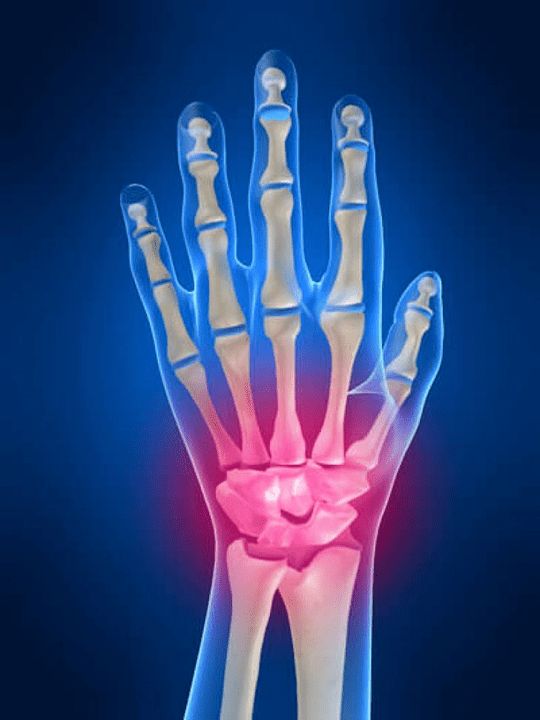

Joint painThe fingers are an indispensable sign of any joint pathology in which the structural components of these joints are damaged.First, pain in the area of these joints can be associated with several autoimmune diseases (Systemic red brightness, rheumatoid arthritis, psoriatic arthritis, etc.) in which immune factors cause harm to their own joint tissues.

The next main reason that can startpainIn fingertips, there may be injuries (bruises, dislocations, bone fractures, ligaments).The pain in these joints can also be caused by degenerative changes that occur in their joint tissues.This can often be observed with osteoarthritis.

What structures can be inflamed in the joints of the hands?

Inflammation is a typical pathological process characteristic of those tissues and organs that were damaged for any reason.It is worth remembering that, in most cases, each disease (For example, gout, rheumatoid arthritis, etc.) or traumnerves, muscles, tendons, subcutaneous fat, skin) Structures.

The following joint structures can be inflamed in the joints of the hands:

- joint cartilage;

- Squeezing bone tissue;

- Board capsule;

- Joint ligaments.